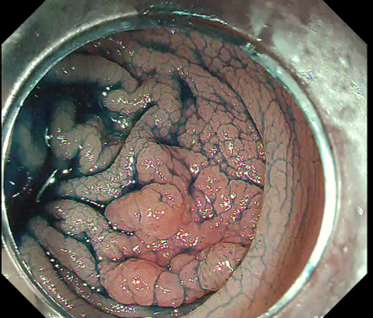

[Case 1] Rectal Ra LST-NG-PD 15 mm

Let’s begin with a relatively basic case (Fig. 2a).

Introduction into the submucosal layer is widely regarded as difficult in colorectal ESD. What physicians mean by this is that it can be hard to penetrate the endoscope into the submucosal layer. In this regard, the initial local injection is crucial. If the local injection reliably elevates the lesion and causes the proximal part of the lesion to swell like a bun, then the first incision can open up the optimal layer immediately. When performing the initial local injection, focus on creating the “shape” of that injection yourself.

Fig. 2 shows the initial phases of case 1, illustrating how a properly executed local injection allows wide spreading with a single incision and facilitates subsequent introduction into the submucosal layer.